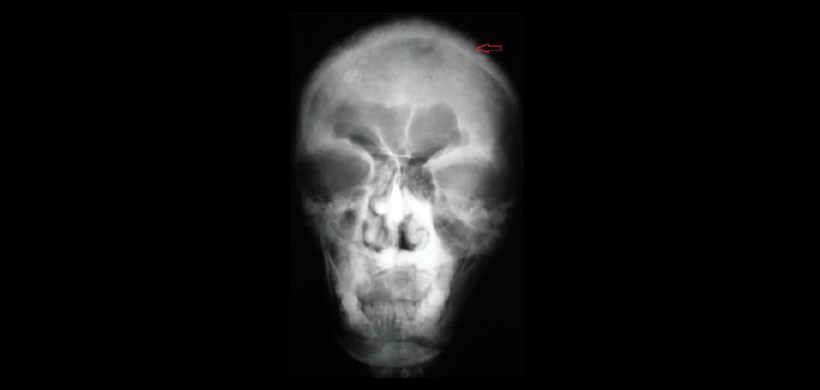

Fig 2. Vista posteroanterior del cráneo, revelan opacificación del antro maxilar, radiopacidades de forma irregular que involucran todo el cráneo, Dando una apariencia de copos algodón.